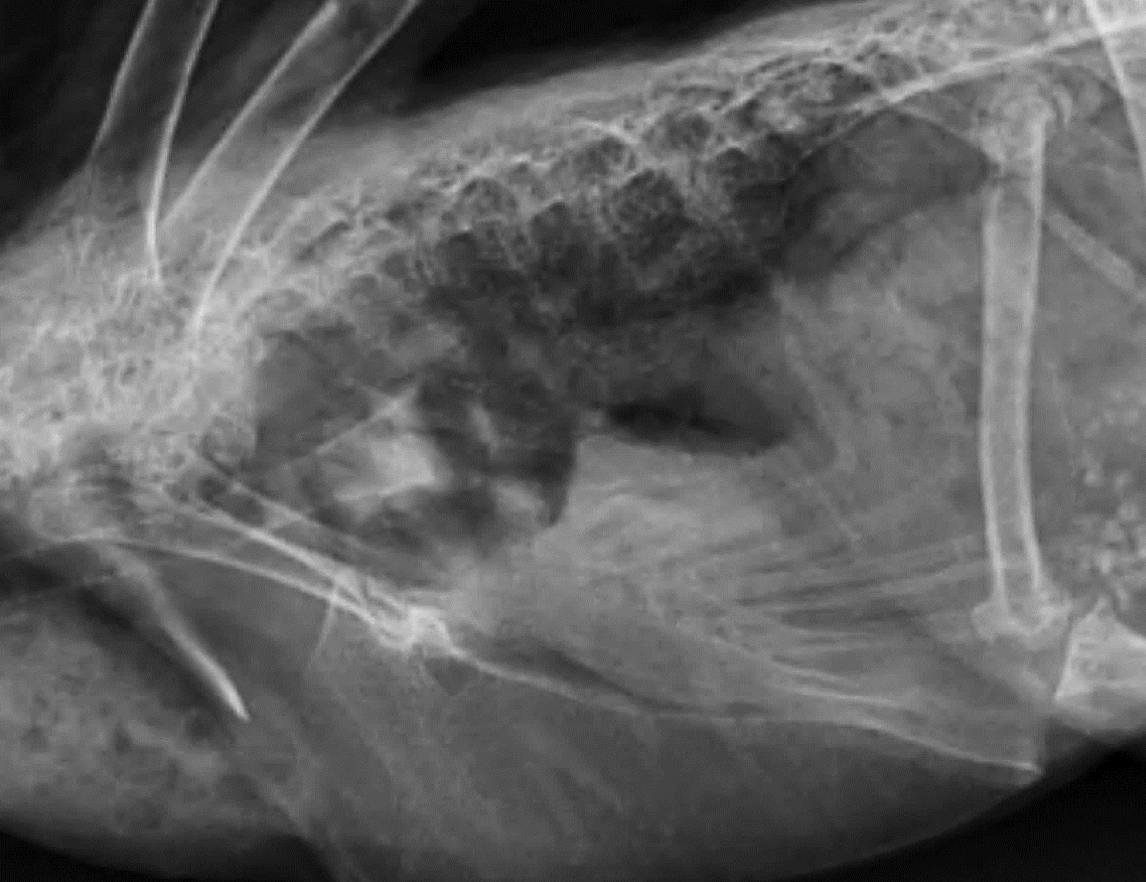

Whats wrong?

pneumonia